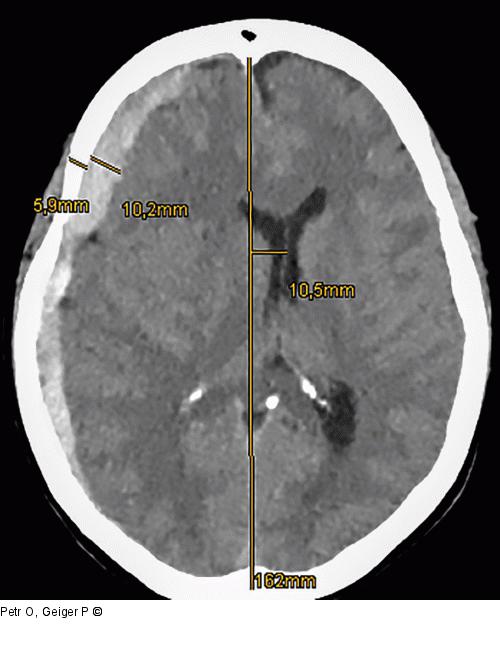

Abbildung 1: Akutes Subduralhämatom Akutes Subduralhämatom (aSDH) bei einer Patientin nach behelmtem Fahrradsturz. Hämatomdicke von fast doppelter Breite der Schädelkalotte und mehr als 1 cm Mittellinienshift. |

Akutes Subduralhämatom (aSDH) bei einer Patientin nach behelmtem Fahrradsturz. Hämatomdicke von fast doppelter Breite der Schädelkalotte und mehr als 1 cm Mittellinienshift. |